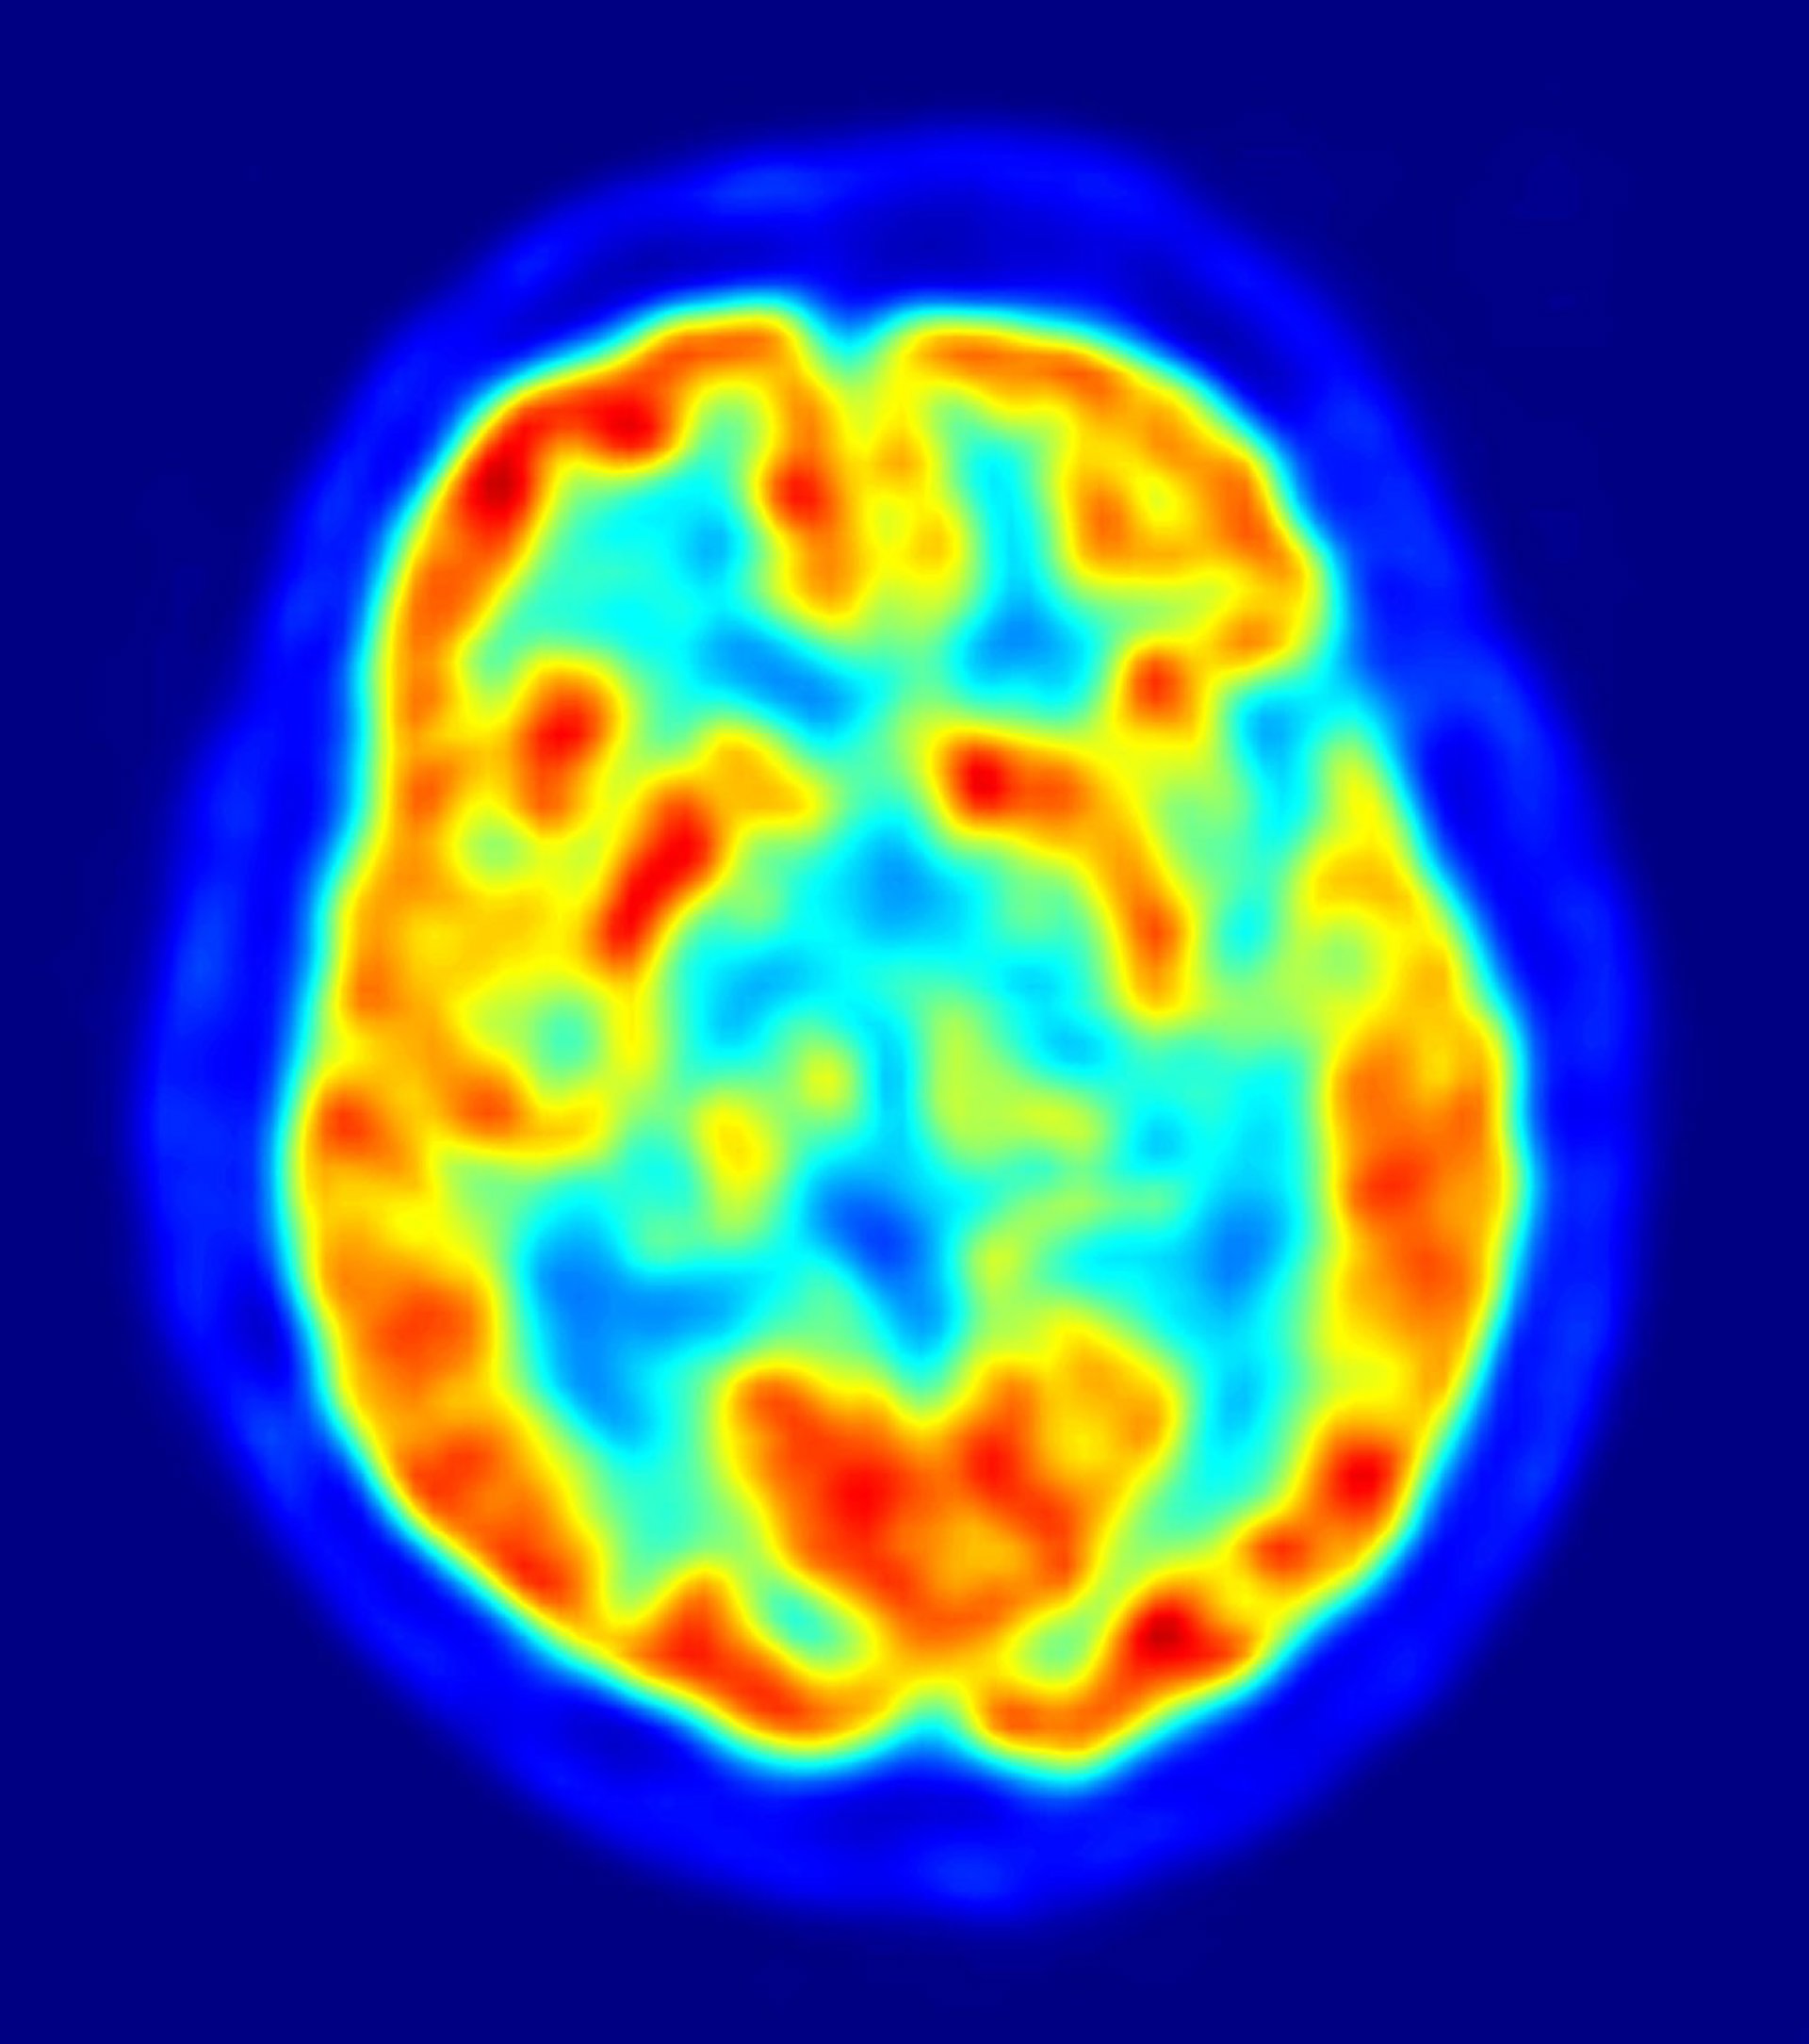

Estudian la relación entre el sistema inmune del cerebro y el Alzheimer

Investigadores del Grupo de Fisiopatología de la Enfermedad del Alzheimer del área de Neurociencias del Instituto de Biomedicina de Sevilla (IBIS) están analizando cómo retrasar las consecuencias del Alzheimer mediante el estudio de las células microgliales, que forman parte del sistema inmune del cerebro y que se activan de forma "excesiva" con la aparición de la enfermedad.

El objetivo es esclarecer si la respuesta inmune puede estar implicada en la degeneración de las células neuronales y con ello diseñar una posible terapia para retrasar los efectos de la patología. En este sentido, los expertos emplean técnicas de bioquímica, biología molecular y biología celular, es decir, cultivos de tejidos, animales transgénicos, muestras humanas y preparando nuevos animales para ver cómo se comporta el sistema inmune cerebral.